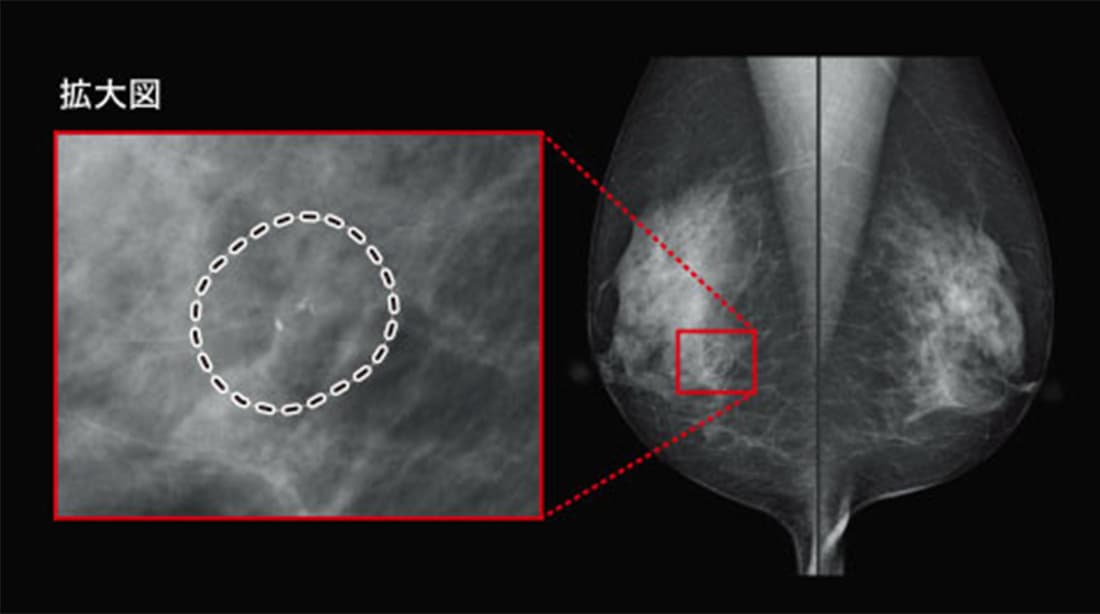

【症例2】 ごく少数の微小石灰化

非常に淡い石灰化が4つほど検出されています。分泌型の石灰化ということで経過観察にする判断もありうると思いますが、これとよく似た病変で実はHER2陽性乳がんの初期段階と判明した症例があったことを想起し、要精査としました。CADが注意喚起してくれた事例です。